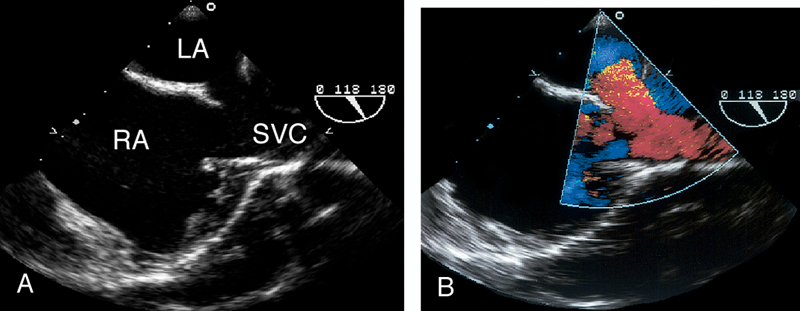

فحوصات تشخيصية لبعض امراض القلب والشرايين التاجية